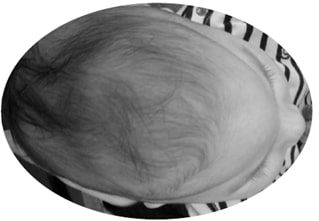

Também conhecida como trigonocefalia, a cranioestenose metópica determina um formato triangular da região frontal.

Como a maior parte do volume cerebral da criança é estabelecido por volta de 12-18 meses de vida, quando uma sutura se fecha antes do momento ideal, pode ocorrer alteração no formato craniano. No caso da cranioestenose metópica, ocorre uma restrição do desenvolvimento ósseo látero-lateral da sutura, interferindo no formato da testa e gerando um aspecto de quilha (triangular).